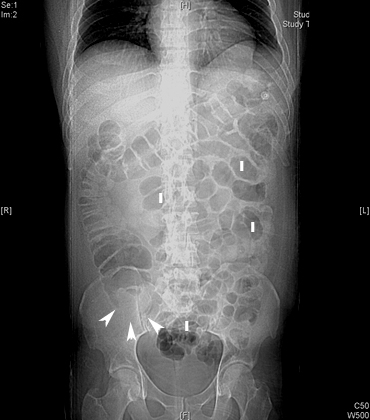

What are the radiological findings of appendicitis in plain abdominal radiograph?

There are no specific signs of appendicitis in plain films but you may see:

- ileus

- appendicoliths

- sentinel loop (dilated adjacent ileum)

- evidence for complications like perforation or appendiceal abscess

- widening and blurring of peritoneal fat line

- right lower quadrant haze due to fluid, edema and mass

- mass indenting the cecum

Acute Appendicitis

Appendicolith

Findings:

- Plain film showing appendicolith.

- Arrow points to ileus.

- Appendicolith may be seen without clinical signs of appendicitis.